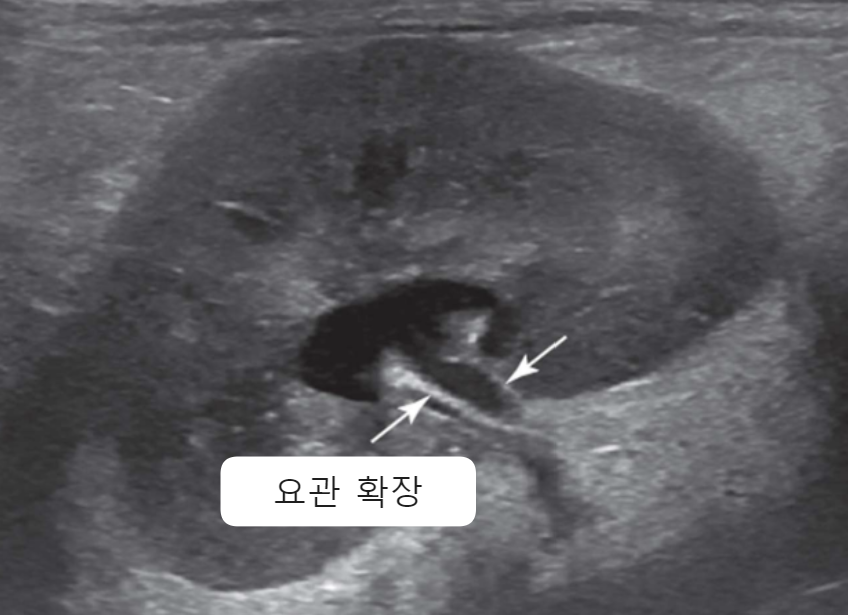

| Ultrasonography (Abd) | _Pyelonephritis |

|---|---|

| - 대표적으로 일시적인 콩팥 비대 (renal pelvic dilation) - Ureteral dilation (요관 확장) - Blunting of the renal papilla (콩팥유두의 둔화) - Echogenic debris (내부에 고에코성 잔해) * 신우신염인데 콩팥이 축소되어 있으면, CKD나 만성 신우신염을 의심해보자. + Bacterial culture : pyelocentesis(신우천자)는 실질을 건드릴 수 있으니, 방광 sampling부터 시도 |